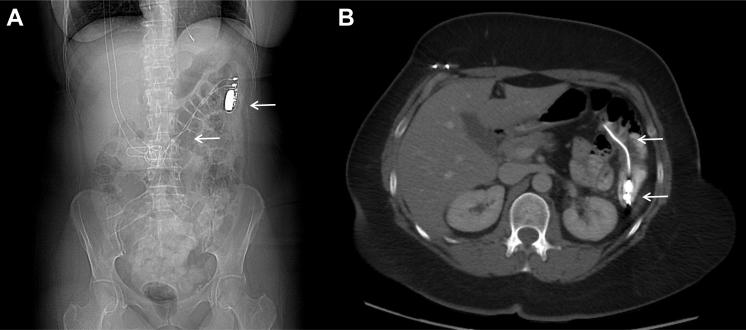

Intracolonic cardiac pacemaker: A case of device migration with colon perforation out of a subcutaneous epifascial pocket.